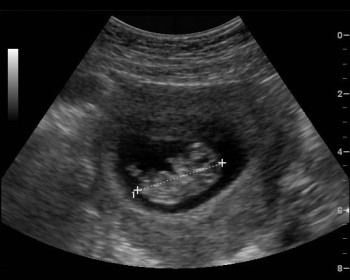

ecografiaL’epidemia di virus Zika in Sud America sta spingendo anche le autorità sanitarie europee a cambiare strategie nella prevenzione. In Gran Bretagna il National Health Service, l’omologo del Servizio sanitario nazionale italiano, ha varato nuove linee guida che suggeriscono – riporta il ‘Telegraph’ – un’ecografia immediata per le donne in gravidanza di ritorno dai Paesi colpiti dal virus, o che hanno viaggiato in zone a rischio.

“Queste donne saranno attentamente monitorare anche se non hanno mostrato segni di un’infezione – sottolineano gli esperti – e saranno sottoposte subito ad una ecografia. Per chi invece ha i sintomi della malattia, l’esame ecografico sarà mensile fino a quando non risulterà negativo alla patologia”. Il sospetto, infatti, è che l’infezione contratta in gravidanza possa essere associata al rischio di microcefalia per il nascituro.